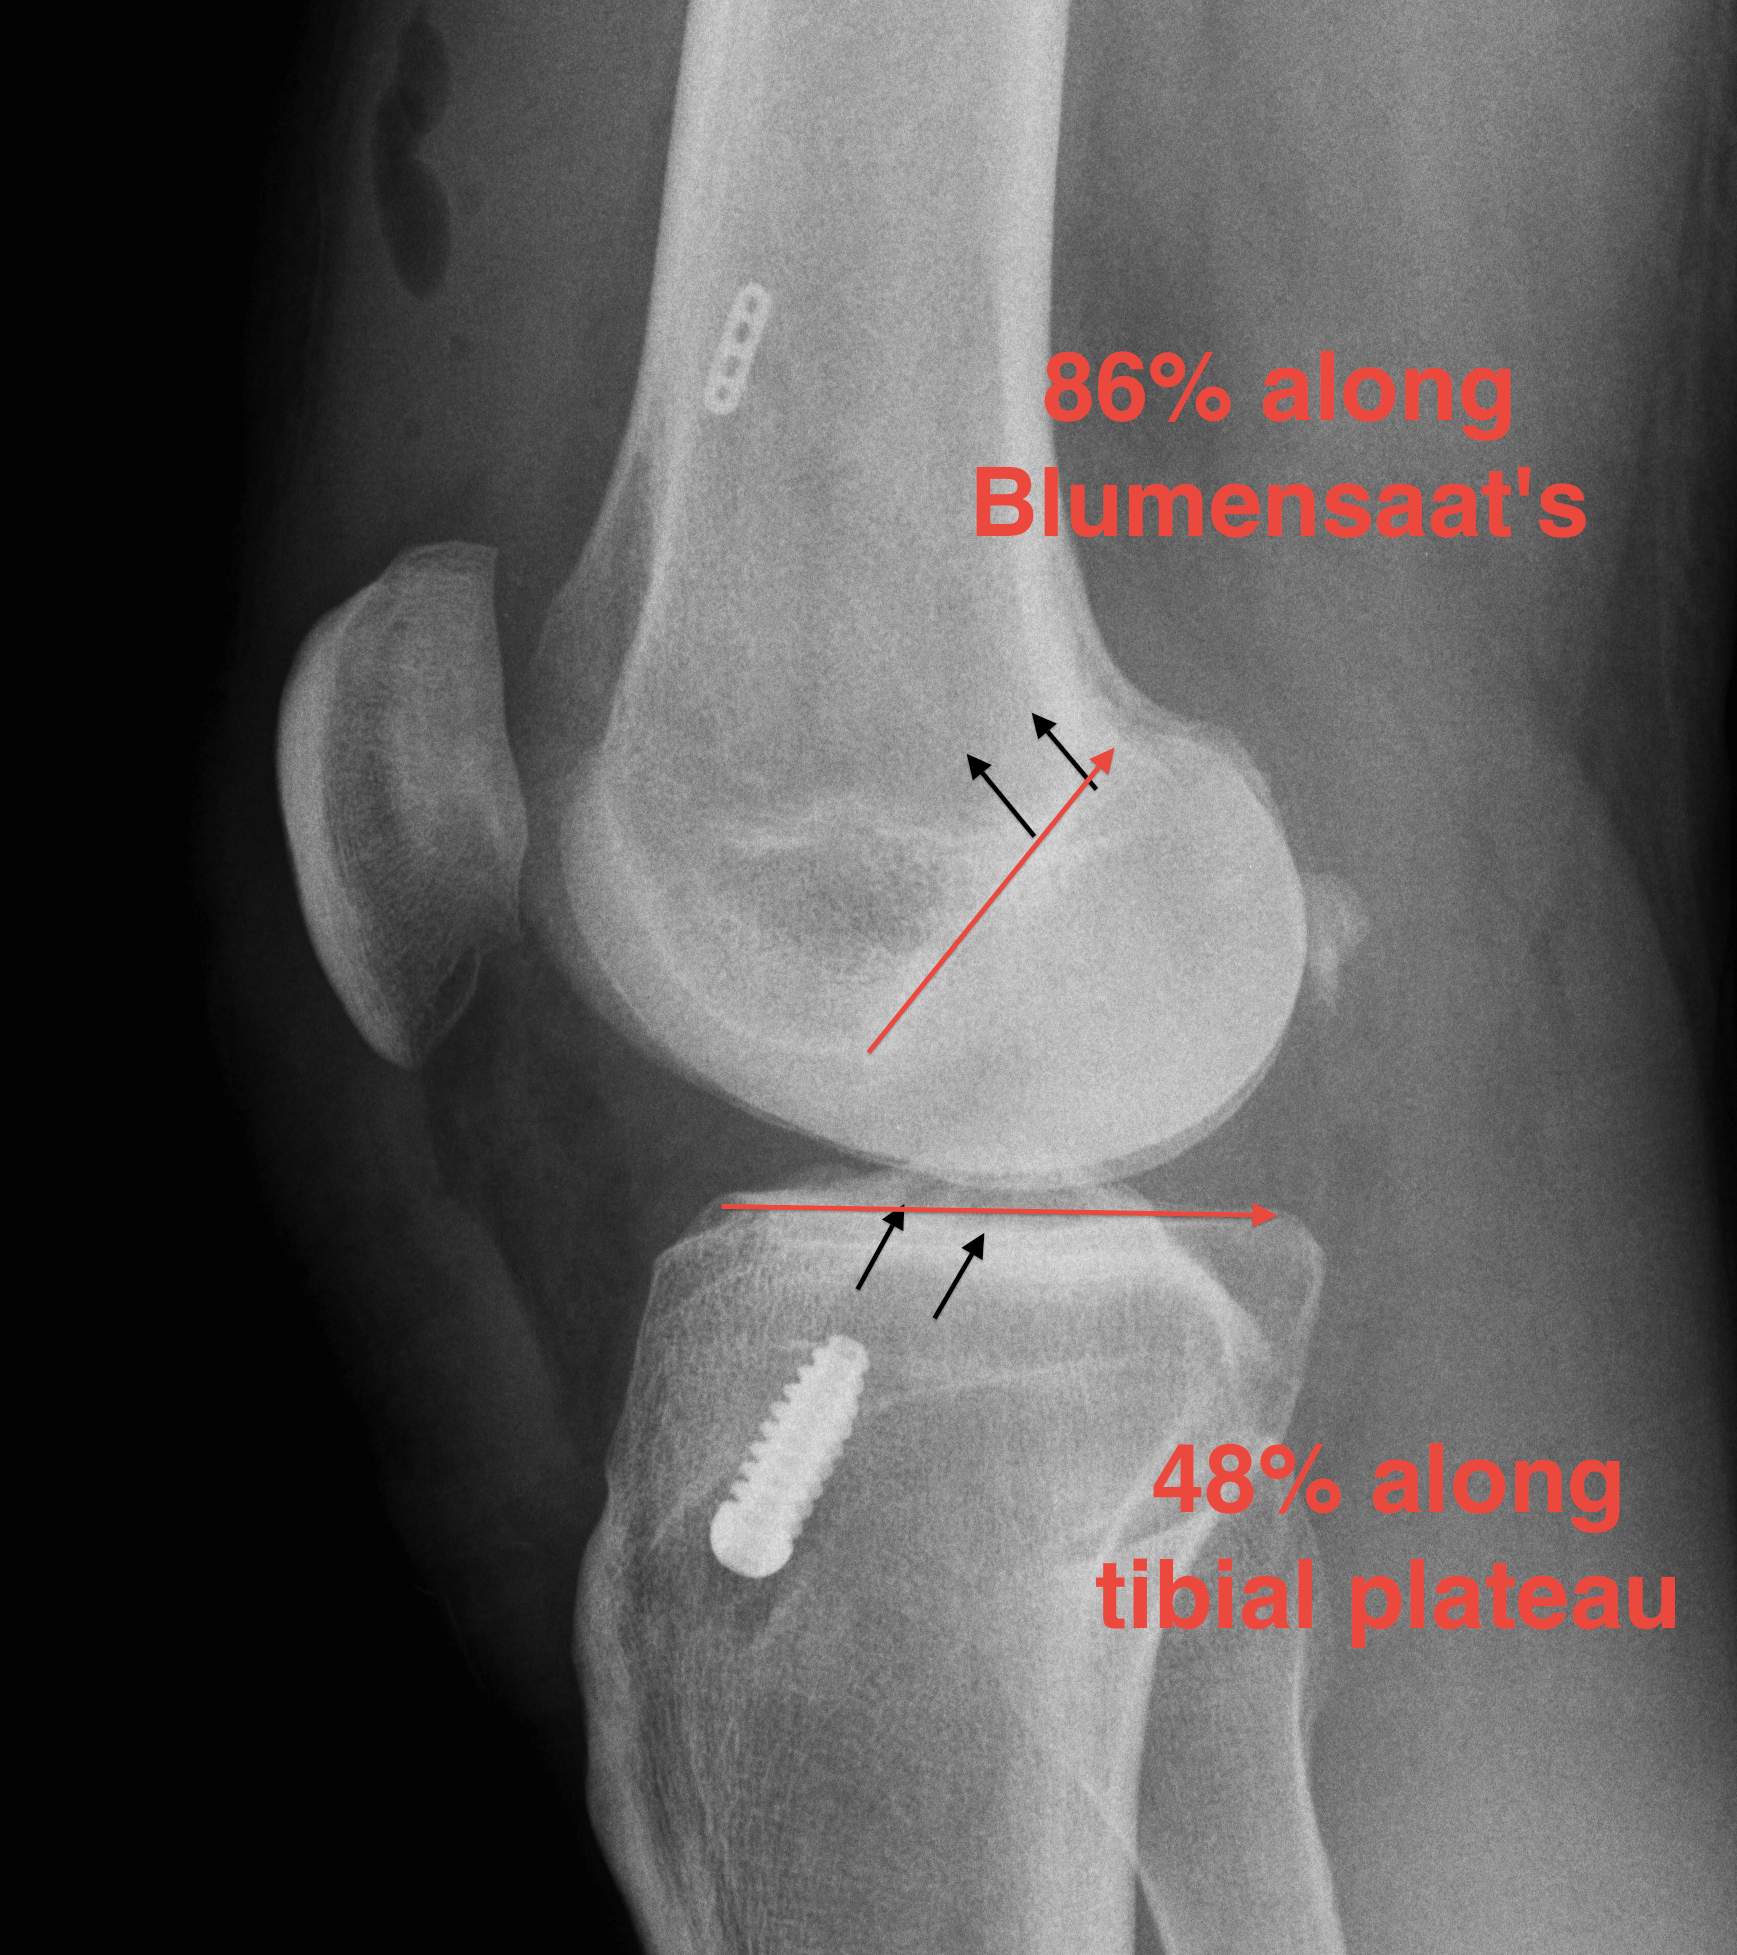

2. X-ray assessment

Lateral x-ray

Femoral tunnel

- intersection of line posterior femoral cortex and Blumensaat's line

Tibial tunnel

- posterior to Blumensaat's line in full extension

- parallel to Blumensaat's line

Pinczewski JBJS Br 2008

- 200 patients followed up over 7 years

1. Posterior femoral tunnel placement

- 86% along Blumensaat's line

2. Anterior tibia tunnel placement

- 48% along tibial plateau

- parallel to Blumensaat's